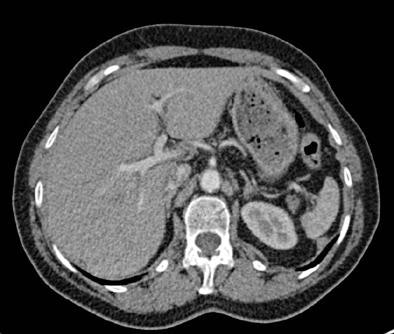

Filtered back projection (FBP) was applied to the full dose images obtained using data from both x-ray tubes, while half-dose datasets were reconstructed from only one tube-detector system, effectively halving the dose. The SAFIRE technique (set at strength 3 from a range of 1-5) was applied to the half-dose images and FBP was applied to the full-dose (two tube) images.

Noise that deteriorated image quality occurred in 24/25 (96%) of the half-dose FBP images but not in full-dose FBP and HD-raw databased iterative reconstruction datasets (p < 0.001), the authors reported. Other artifacts occurred with similar prevalence among the datasets, they said, and no significant differences were found between the three image datasets for the presence or absence of other artifacts besides noise (p > 0.05). The inter-reader agreement for image quality analysis was moderate to good (kappa = 0.579 - 0.701).

Finally, sharpness of the aortic contour was found to be significantly better for the full-dose FBP (median score 1) and half-dose SAFIRE (median score 1) versus the half-dose FBP images (median score 2, p < 0.001).